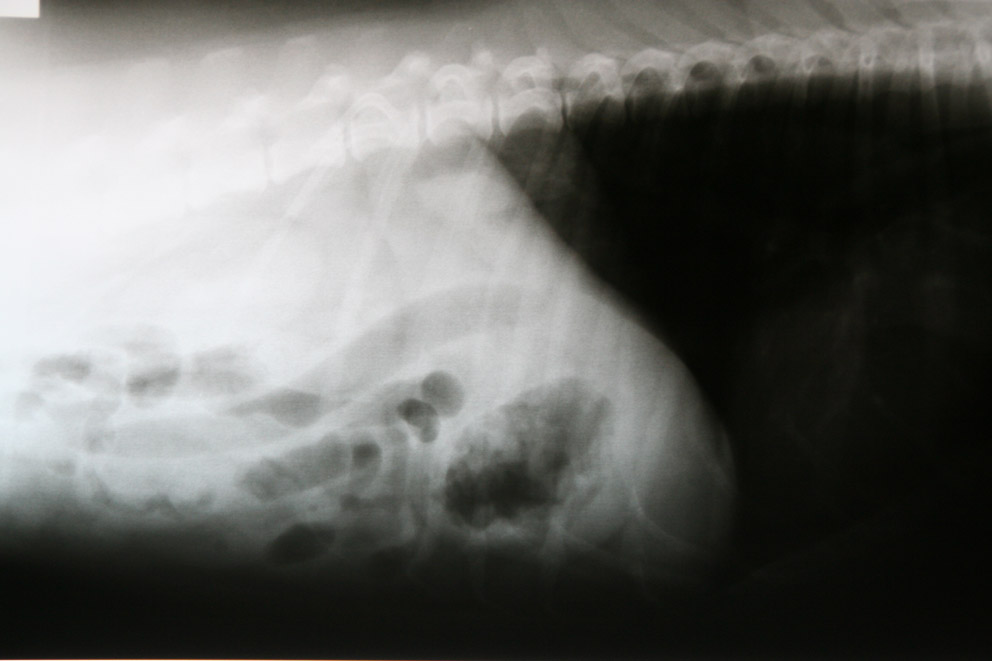

Omdat zo’n vreemd voorwerp zeker wel de oorzaak van de klachten van Fanny zou kunnen zijn en het chronisch braken een reden is voor verder onderzoek, hebben we röntgenfoto’s gemaakt.

Op de ene foto zagen we geen verdachte structuur,